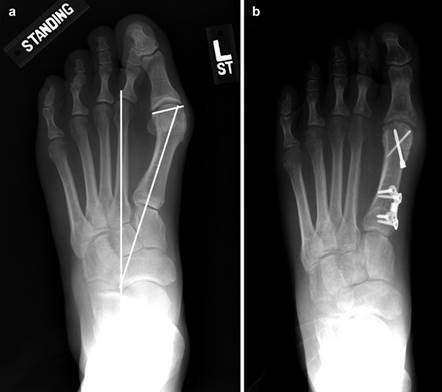

Weight-bearing anteroposterior (AP), lateral, and sesamoid axial radiographs are mandatory. On the AP view, the surgeon measures the Hallux Valgus Angle (HVA, normal < 15°), the Intermetatarsal Angle (IMA, normal < 9°), and the Distal Metatarsal Articular Angle (DMAA). The lateral view is scrutinized for Meary's angle (talo-first metatarsal angle) to identify midfoot collapse, as well as the presence of dorsal osteophytes indicative of hallux rigidus. The sesamoid axial view is critical for assessing the degree of sesamoid subluxation and the integrity of the crista.

Digital templating software is employed to determine the center of rotation of angulation (CORA) and to simulate the proposed osteotomy or fusion. This allows the surgeon to anticipate the degree of translation required, the potential for metatarsal shortening, and the appropriate size of fixation hardware. For a Lapidus procedure, templating helps calculate the exact wedge of bone to be resected from the medial cuneiform and first metatarsal base to achieve the desired multiplanar correction.

To achieve multiplanar correction, the surgeon must address the sagittal, coronal, and transverse planes. The first metatarsal is plantarflexed to restore the longitudinal arch, rotated out of pronation to realign the sesamoids, and translated laterally to close the IMA. Subchondral drilling or feathering is performed to optimize the biological environment for fusion. Fixation is traditionally achieved with two or three crossed solid or cannulated screws (typically 3.5mm or 4.0mm). Recently, plantar or medial locking plates have gained immense popularity due to their superior biomechanical construct, allowing for earlier weight-bearing. Bone graft or orthobiologics may be packed into the arthrodesis site to stimulate osteogenesis.

Clinical & Radiographic Imaging Archive